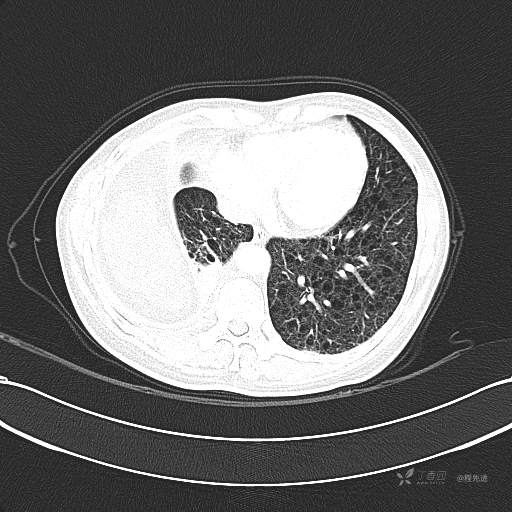

患者性别:女

患者年龄:51岁

简要病史:胸闷半年